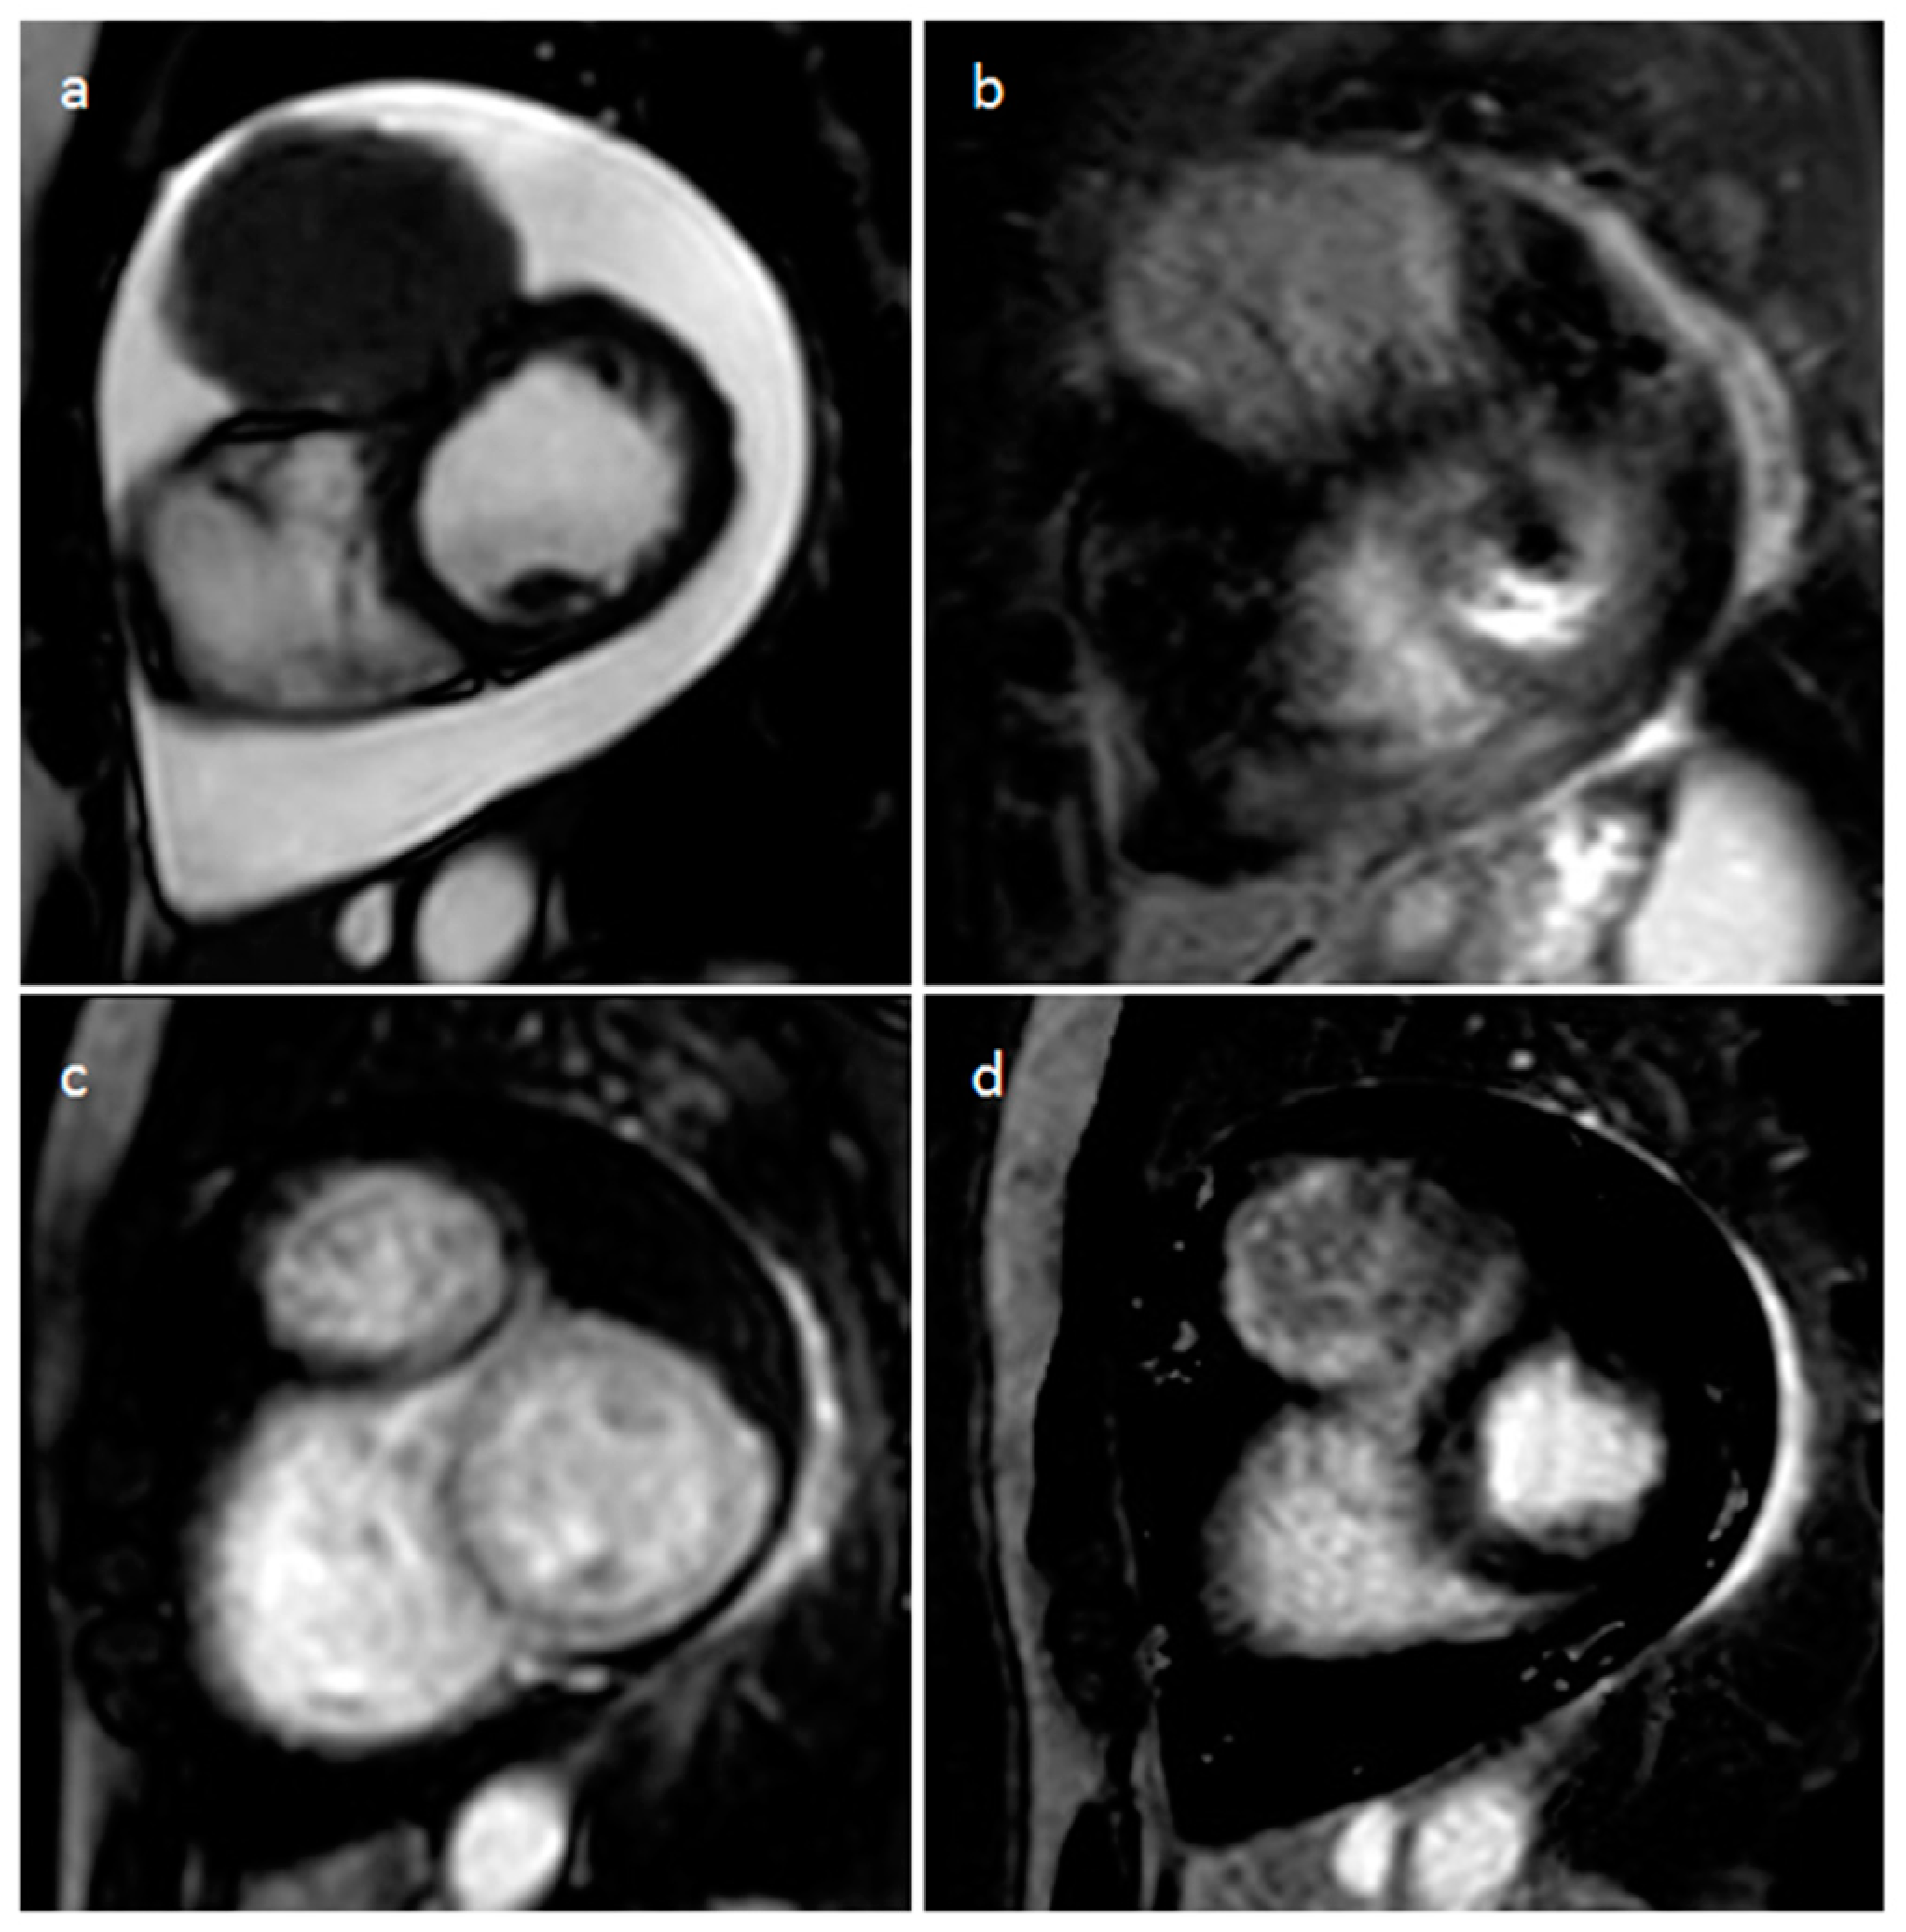

4.1. Myxoma

| Myxoma | Adulthood. Carney complex. | LA | Usually, asymptomatic. Rarely, intracardiac obstruction, embolic events and constitutional symptoms | Mobile mass arising from the IAS | Globular or spherical, with a friable surface and heterogeneous internal echogenicity | Heterogeneous, low attenuation, may be calcified | Isointense T1w, High T2w, heterogeneous LGE |